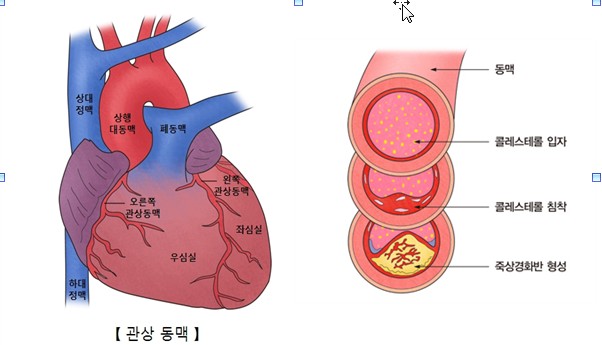

오늘은 정말 많은 분들이 놓치기 쉬운 **치명적인 심장 질환, ‘심근경색’**에 대해 이야기해보려 합니다.심근경색은 말 그대로 심장 근육이 괴사하는 질환으로, 골든타임을 놓치면 생명을 잃을 수 있는 응급상황입니다.

심장 혈류가 막히는 순간, 몸이 위급 상황으로 인식하여 자율신경 반응으로 식은땀을 흘리게 됩니다.